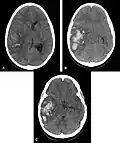

- Hémorragie cérébrale : la principale manifestation clinique de l'angiopathie amyloïde est l'hémorragie intracérébrale de topographie lobaire ou cérébelleuse[7]. La topographie lobaire regroupe les structures corticales et sous-corticales (c'est-à-dire proches de la surface du cerveau). Elle est principalement définie par opposition à la topographie profonde qui englobe essentiellement les ganglions de la base (en particulier le thalamus ou le noyau lenticulaire) et le pont. Cette distinction topographique est importante dans la mesure où l'hémorragie cérébrale lobaire est très évocatrice d'AAC alors que l'hémorragie cérébrale profonde est plutôt évocatrice de microangiopathie hypertensive. Cette distribution reflète l'atteinte préférentielle des petits vaisseaux corticaux dans l'AAC et de artères lenticulo-striées dans l'angiopathie hypertensive[8]. Cependant, parmi l'ensemble des topographies lobaires possibles, l'atteinte du lobe temporal ou occipital semble prédominante, en particulier si le patient avait déjà présenté une hémorragie dans ces régions[9]. Comme pour l'ensemble des AVC, les symptômes associés aux hémorragies cérébrales de l'AAC sont variables. Ils dépendent avant tout de la taille de l'hémorragie et de sa localisation.

Scanner cérébral objectivant une hémorragie lobaire temporale droite évocatrice d'une possible angiopathie amyloïde

Scanner cérébral objectivant une hémorragie profonde (thalamique gauche) plutôt évocatrice d'une angiopathie hypertensive